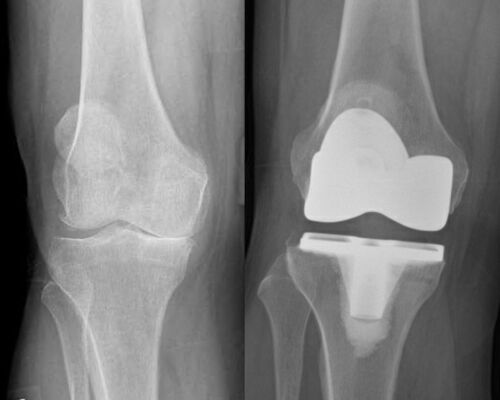

JOINT REPLACEMENT / ARTHOPLASTY

Advanced knee arthritis – left image,

Total knee replacement – right image